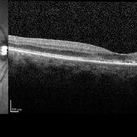

Plaquenil Toxicity OCT

Dec 6 2016 by Courtney Crawford, MD, FACS

70-year-old woman with history of plaquenil use for rheumatoid arthritis.

Condition/keywords: plaquenil toxicity